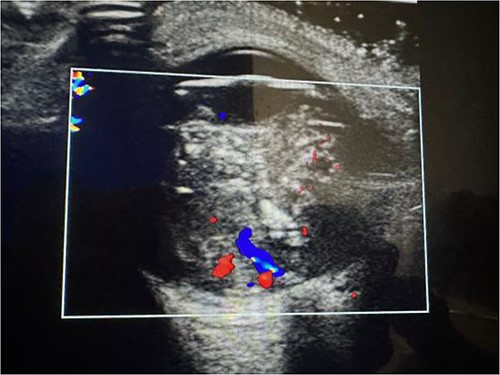

The laboratory examination’s results revealed a low hematocrit of 27 and a low hemoglobin (HB) of 8.5 mg/dl. Orbital ultrasonography revealed a hyper-echogenic tumor in the left eye with vitreous seeding (Fig. 2), while the orbital MRI showed a left intraocular mass of 10.10 mm by 8.7 mm with medium intensity in T1W/FLAIR sequences and a low intensity in T2W images (Fig. 3). The lesion has a slightly heterogeneous contrast enhancement in the post-contrast sequence with group D international classification of Rb (ICOF) stage I. The radiological findings most likely indicated Rb. Tumors occupied 50% of the globe, but there was no subretinal detachment. Fortunately, the tumor has not affected the optic nerve. An enucleation procedure (removal of the whole contents of the eye) under general anesthesia was performed (Fig. 4). Histopathological examination showed hyperchromatic small round blue cells with scant cytoplasm arranged in sheets, nests, and Flexner–Wintersteiner rosettes with histologic G3 with endophylitis, tumor necrosis, and calcification (35% of calcification is eosinophilic) that was consistent with Rb (Fig. 5). After 3 months of follow-up in the outpatient department, a prosthetic eye was implanted for cosmetic purposes (Fig. 6).

Coronal orbital MRI of t1 and t2 shows left intraocular tumor with vitreous seeding.